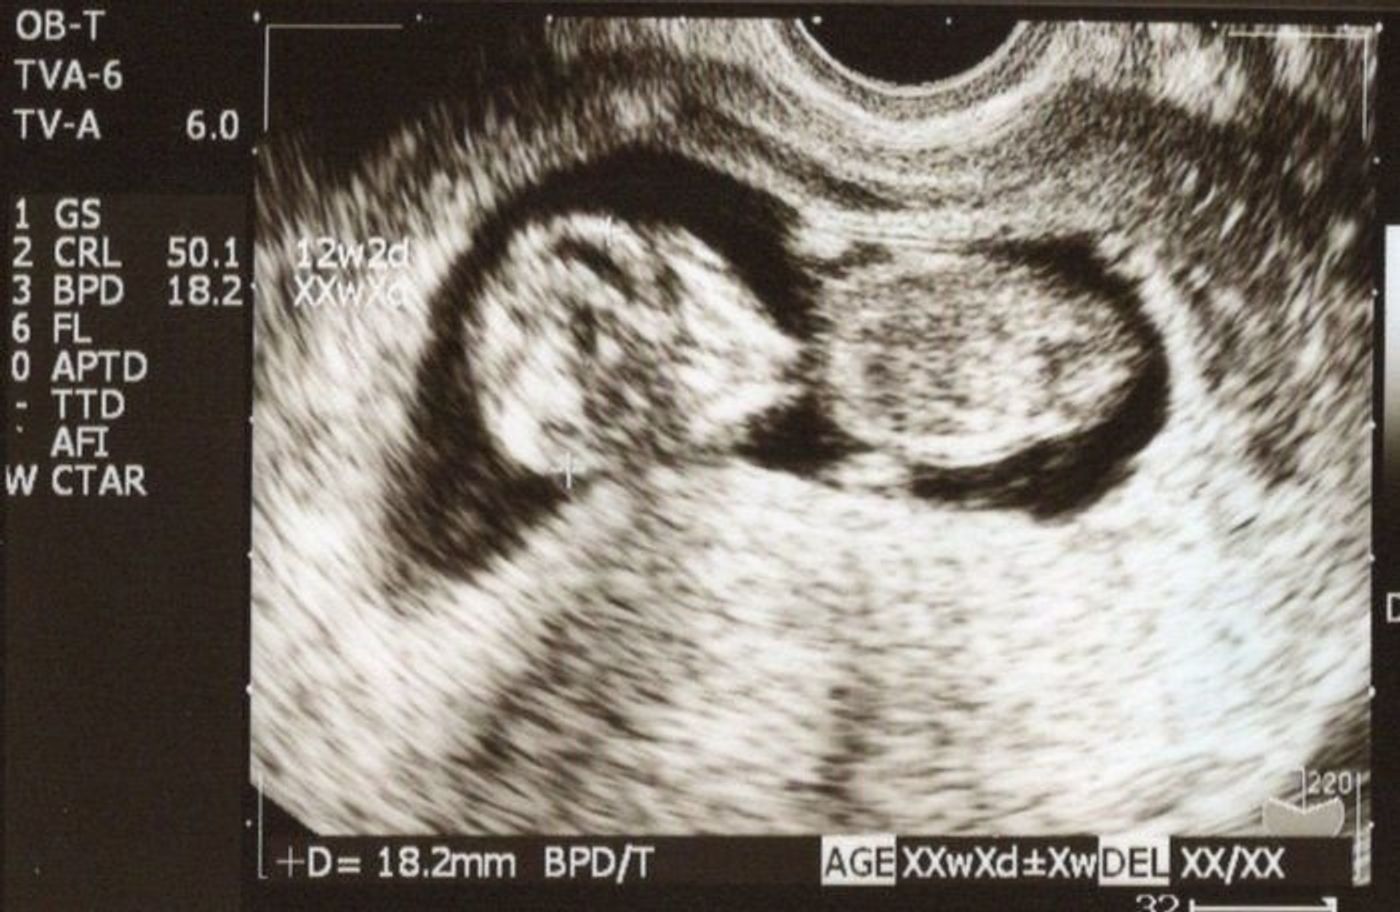

妊娠週数は4週で1ヶ月とし、 最終月経の初日を0日として数え始めるのが一般的 です。 最終月経の初日を妊娠0日とし、 実質的には妊娠していないときから数え始めます。 妊娠週数8週目から「胎芽」ではなく「胎児」と呼ばれるように。 だんだん人間らしい体つきになり、 エコー写真を見るのも楽しみになってきますよ。 妊娠3ヶ月(妊娠8週、9週、10週、11週)の 胎児と しかし、妊娠12週目で 「胎児の首の後ろが厚い」 と医師に言われました。 医療現場では赤ちゃんの首のむくみを 「NT」 と呼びます。 この、 NTが通常より厚いとダウン症の可能